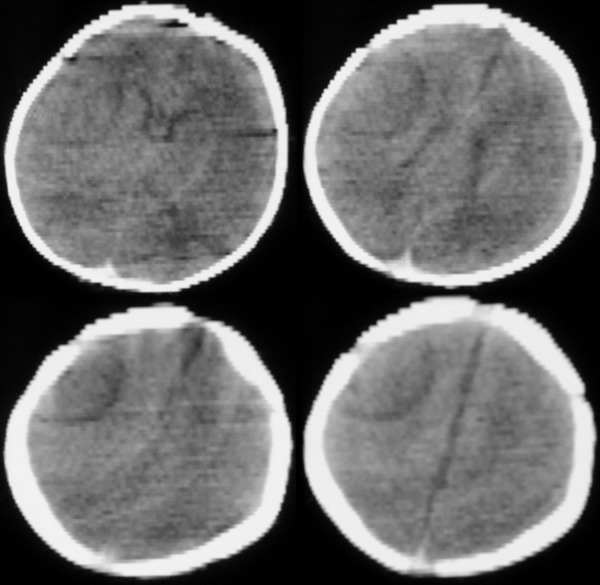

标题: CT2096:[求助]F ,3d, 因重度窒息入院余(--)。 [打印本页]

标题: CT2096:[求助]F ,3d, 因重度窒息入院余(--)。

多发脑水肿表现  考虑脑缺氧缺血脑病

结果:脑缺氧缺血脑病。其它的确是伪影,下午以经排除,真不好意思。幸好没误诊,谢谢分析对的战友!!

关于伪影的问题以前也讨论过。鉴别点就是机器灵敏度校正后“病变”消失;体位改变后“病变”位置随之改变。等等。